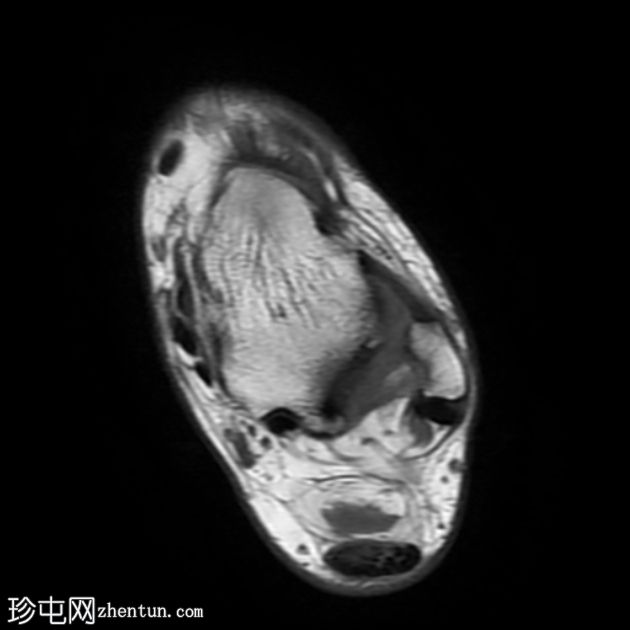

轴向

T1

跟腱插入

,伴有跟腱明显增厚,可诱发异常信号、跟腱后滑囊炎、跟骨后突及骨髓水肿信号。

Haglund综合征的检查结果令人印象深刻。

Haglund综合征是指以下三联征(Haglund三联征):

跟腱插入性病

跟腱后滑囊炎

Haglund畸形(即跟骨后上外生骨疣)